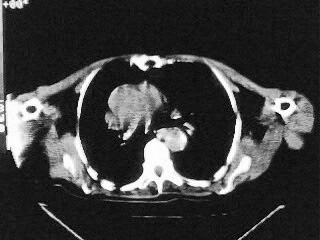

女,79,咳 嗽月余,无其它不适

1)两肺炎症。2)食管裂孔疝可能;建议行上消化道钡餐检查。

后纵隔内左心房至肝左叶后方椎体中线偏左巨大软组织包块,其壁均匀比较薄,其内可见宽气液平。

考虑食管裂孔疝。建议钡餐检查